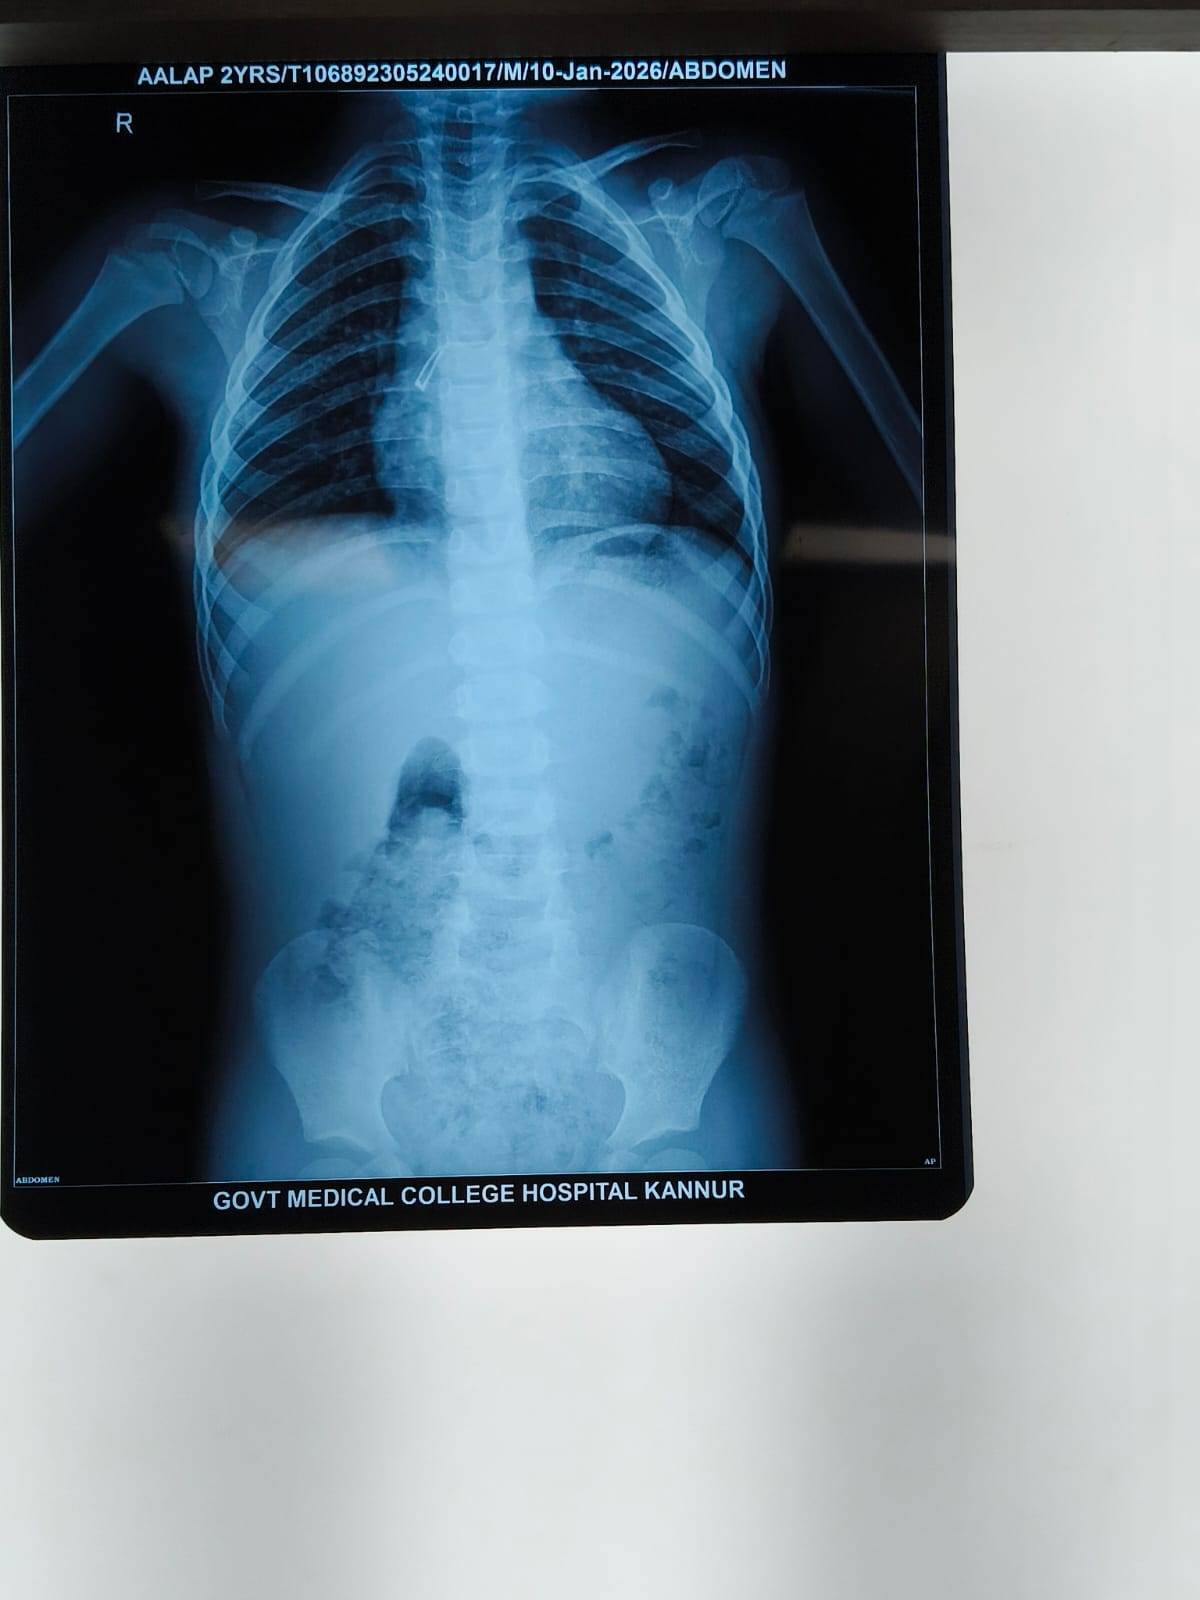

ടിവി റിമോട്ടിലെ എൽഇഡി ബൾബ് ശ്വാസനാളത്തിൽ കുടുങ്ങി ഗുരുതരാവസ്ഥയിൽ എത്തിയ മാതാമംഗലത്തുള്ള മൂന്ന് വയസ്സുകാരന് പരിയാരം കണ്ണൂർ ഗവൺമെന്റ് മെഡിക്കൽ കോളേജിലെ ഡോക്ടർമാർ പുതുജീവൻ നൽകി.

കുട്ടിയെ ശ്വാസതടസ്സ ലക്ഷണങ്ങളോടെ ആശുപത്രിയിൽ പ്രവേശിപ്പിച്ചതിനെ തുടർന്ന് ശിശു ശസ്ത്രക്രിയ വിഭാഗം അടിയന്തരമായി ബ്രോങ്കോസ്കോപ്പി ശസ്ത്രക്രിയ നടത്തി ബൾബ് വിജയകരമായി പുറത്തെടുത്തു. ഏറെ സങ്കീർണ്ണമായ ശസ്ത്രക്രിയയ്ക്ക് ശിശു ശസ്ത്രക്രിയ വിഭാഗത്തിലെ ഡോ. വരുൺ ശബരി നേതൃത്വം നൽകി. ഡോ. അനു, ഡോ. നാഗദിവ്യ എന്നിവർ അനസ്തേഷ്യ നൽകി. സിസ്റ്റർ ബബിത ശസ്ത്രക്രിയക്ക് സഹായിയായി. ചികിത്സയ്ക്ക് ശേഷം കുട്ടിയെ പിറ്റേ ദിവസം തന്നെ ആശുപത്രിയിൽ നിന്ന് ഡിസ്ചാർജ് ചെയ്തു.